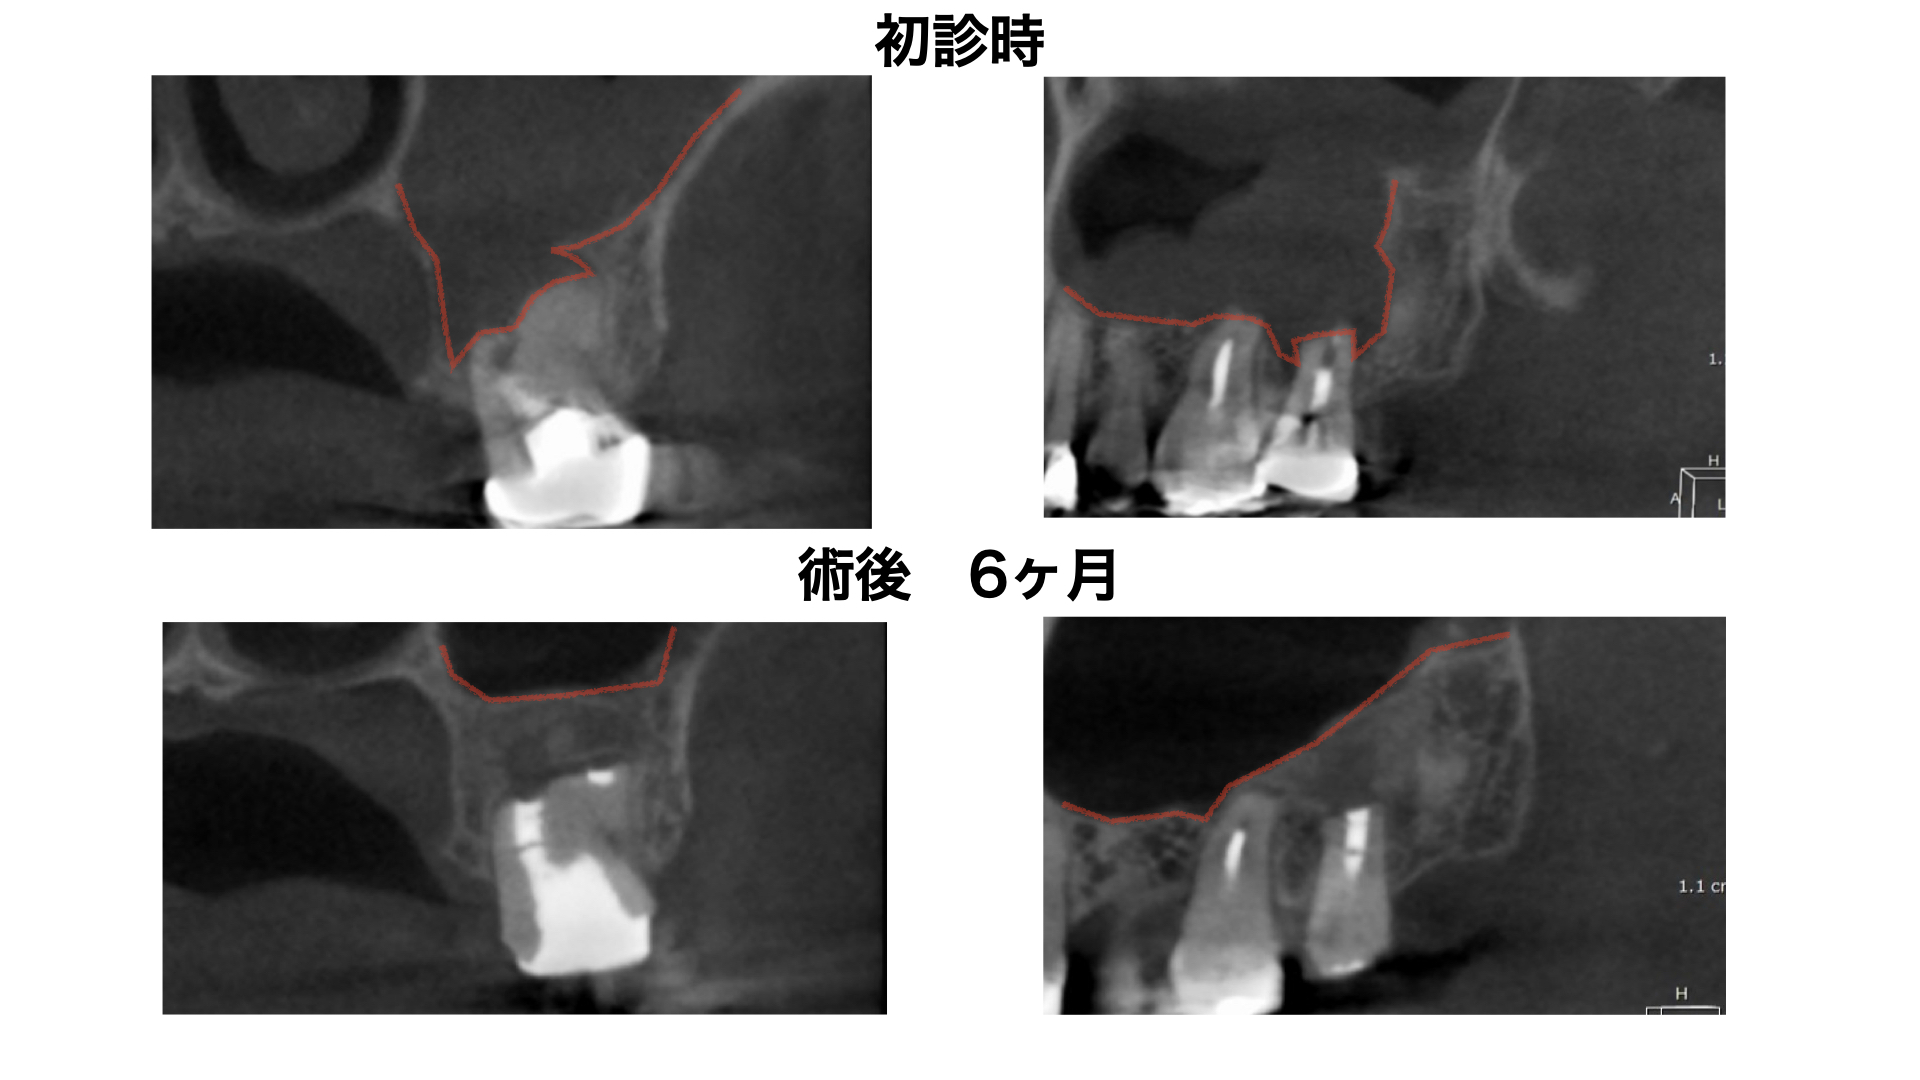

経過観察 6ヶ月後

術後比較

- 上顎洞炎の消失を確認するため6ヶ月以上の経過観察を必要とする。